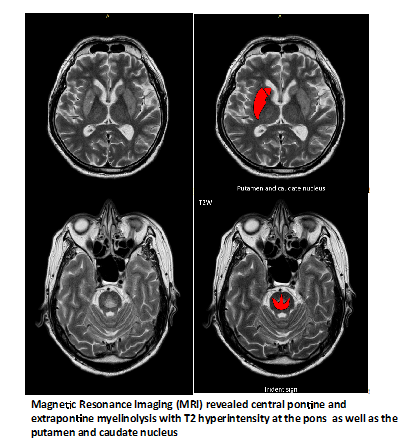

A 52-year-old man on several anti-hypertensives including Hydrochlorothiazide and Spironolactone presented with confusion and intestinal obstruction. He had profound hyponatremia with serum sodium of 96 mmol/L; this was attributed to the diuretics he was prescribed. Clinical improvement were seen over the next six days with gradual correction of serum sodium at a rate of around 4 mmol/L/day, from 96 mmol/L to 124 mmol/L. However, over the following three days, serum sodium increased further from 124 mmol/L to 147 mmol/L. Approximately 48 hours after the rapid increase in serum sodium, his Glasgow Coma Scale decreased indicating low conscious level, thus necessitating intubation. Serum sodium levels stabilised thereafter, but there were no improvement in conscious level. The patient appeared to be in a ‘locked-in’ state. Magnetic Resonance Imaging (MRI) (shown below) revealed central pontine and extrapontine myelinolysis with T2 hyperintensity at the pons (Trident sign) (A) as well as the putamen and caudate nucleus (B) and restricted diffusion on Diffusion Weighted Imaging (DWI) mapping (C) and Apparent Diffusion Coefficient (ADC) mapping (D). These are radiological features, which has been described.1–3 Plasma exchange was done, but he showed no significant neurological recovery (Figure 1 & 2).